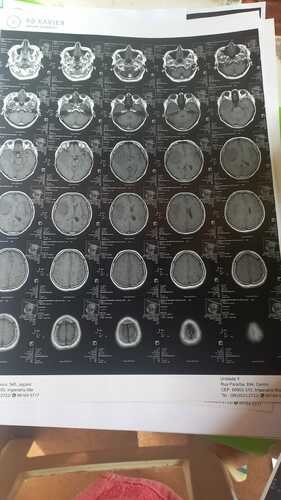

Recentemente, Maria do Socorro recebeu o diagnóstico devastador de um tumor na cabeça. Esta notícia abalou não só ela, mas todos nós que a amamos e admiramos. No entanto, Maria do Socorro é uma lutadora e está determinada a vencer esse tumor.